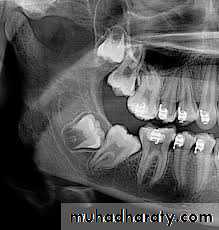

Impacted first and second molars

These are uncommonly impacted, their management consist of surgical extraction through a buccal flap, bone removal avoiding damage to the inferior dental nerve that may cross buccal to the neck of the teeth, sectioning of the tooth may be necessary. The indications of surgical treatment include symptomatic teeth, those that have caused infections, or have evidence of radiographic changes such as cyst or resorption of adjacent teeth roots.Rarely all the three mandibular molars or the second and the third molars are impacted, in this case we start with the mesial of the two and the middle of the three.

Another line of treatment is the surgical up-righting, especially of the impacted second molar. This is done through buccal approach, the tooth is exposed carefully without exposing the CEJ, if the third molar is present it needs to be removed, if not, bone posterior to the second molar is removed, followed by tipping the tooth slightly posteriorly and superiorly, and the tooth can be allowed to erupt spontaneously. This procedure is better carried out when 2/3 of the roots of the impacted second molar are developed. Teeth with fully developed roots have poor prognosis for this procedure

Usually there is no need for fixation but RCT may be needed 6-8 weeks after surgery, also there should be no occlusal forces on the tooth in the postoperative period. Follow up for about 2 years is necessary.